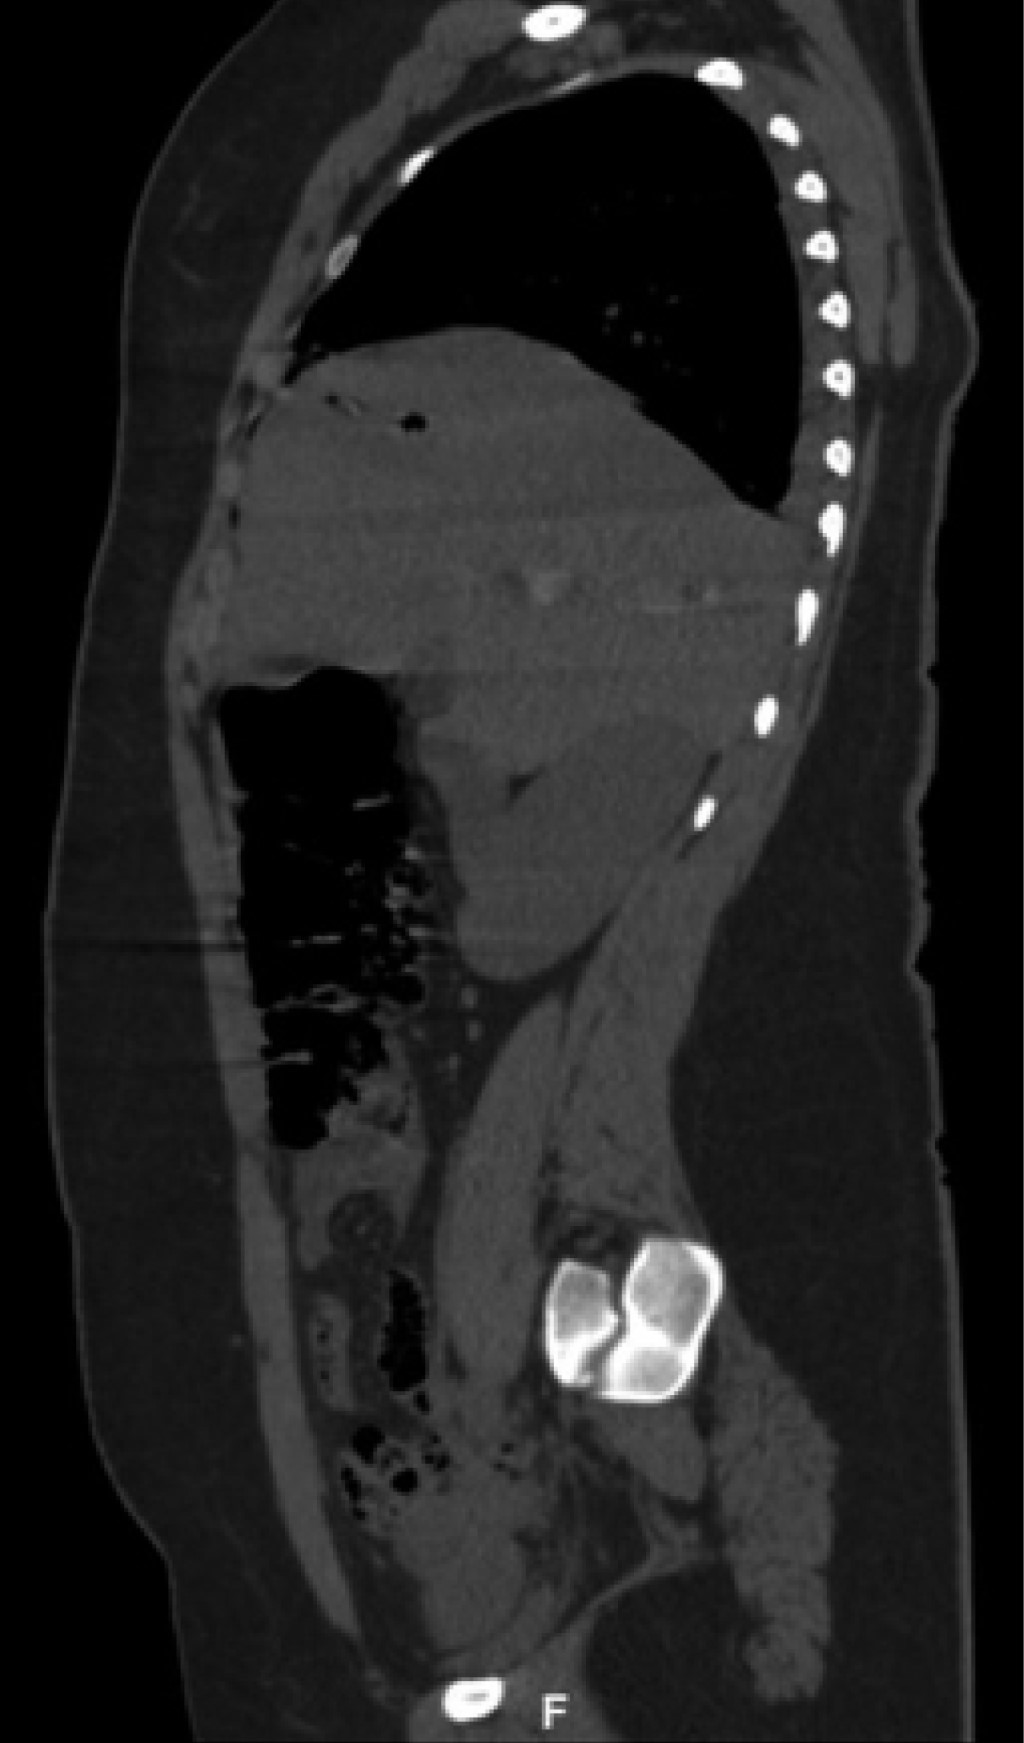

On physical examination, her vital signs were as follows: heart rate of 74 beats/minute; blood pressure of 98/67 mmHg; respiratory rate of 19/min; temperature of 36o C; and oxygen saturation of 98%. The chest showed a PAF entry orifice in the upper outer quadrant of the right breast (Figure 1), and the lung fields were well-ventilated. The abdomen was flat, with peristalsis, soft and painless to palpation. The blood cytology reported a hemoglobin of 12.8 g/dL, hematocrit of 36.4%, and white blood cells of 6,400/ml. The chest X-ray ruled out pneumothorax (Figure 2). A CT scan of the thorax and abdomen showed a metallic foreign body lodged in the right parasagittal line at the level of the 12th thoracic vertebra (Figure 3), without pulmonary or diaphragmatic lesion (Figures 4 and 5); in the abdomen, a PAF tract was observed with a 12 cm by 2.3 cm grade IV liver lesion in segments IV, VII and VIII of Couinaud (Figure 5), scarce free fluid, without lesion of any other organ (Figures 3, 5 and 6). Twenty-four hours later, a control CT scan was performed, showing the liver lesion without subcapsular collection or active extravasation on the application of contrast medium, without an increase of free fluid. Given the correlation of these findings with clinical stability, the patient was discharged on the fourth day of her admission. She did not have any complications one month after her discharge.

Figure 2